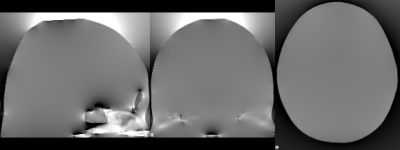

B0 inhomogeneities

B0 inhomogeneities occur at interfaces of materials with different magnetic susceptibilities, such as tissue-air interfaces. These differences lead to distortion in the local magnetic field, as Maxwell’s equations need to be satisfied (an example of the distorted field is shown in the image to the right).